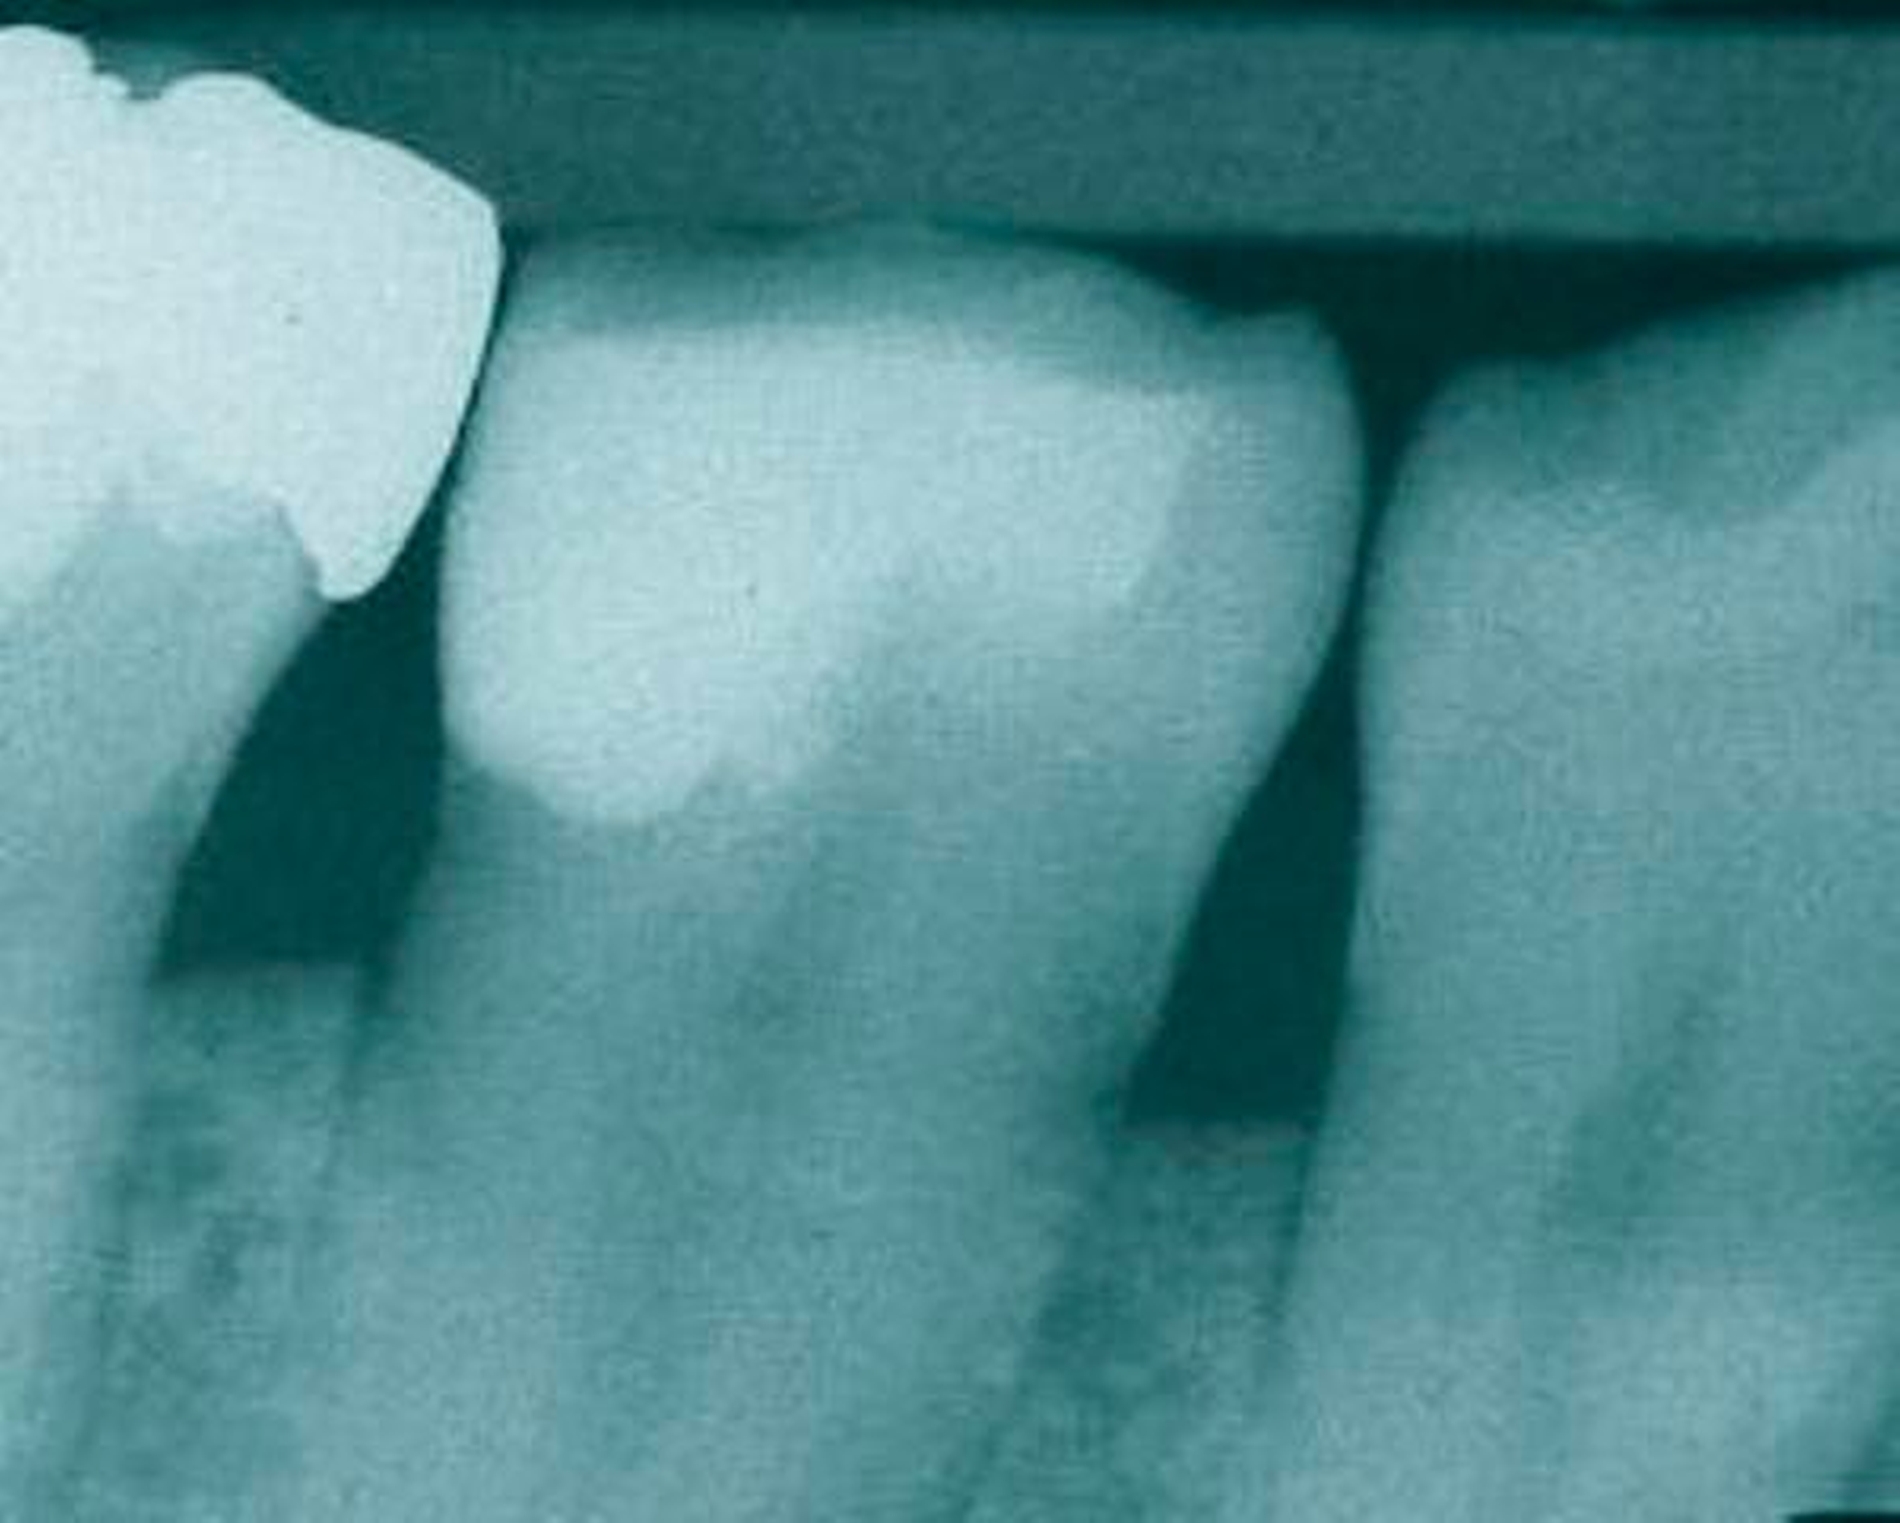

Abbildung 4: Überwachtes Monitoring (Belassen und Beobachten) von Zahnlücken

In der Zahnmedizin ist ein Dogma weit verbreitet: „Jede Lücke muss rasch geschlossen werden.“ Tatsächlich gibt es jedoch viele Situationen, in denen es ohne relevante funktionelle und ästhetische Einbußen vertretbar erscheint, eine Lücke zu belassen und regelmäßig zu beobachten (Monitoring). Derzeit erfolgt die Entscheidung „Lücke belassen versus Lücke schließen“ oftmals subjektiv. Sie ist zuweilen weniger von den Patientenvariablen abhängig als von den Schwerpunkten der betreuenden Zahnärzte (Abbildung 4) [Listl et al., 2016]. Ein fachlich fundiertes Vorgehen, das eine Entscheidung unter einer Nutzen-Risiko-Abwägung trifft und ein Monitoring in die Überlegungen einbezieht, kann ebenfalls in die Kategorie der frugalen Interventionen eingeordnet werden. Gleiches gilt für ein Vorgehen im Sinne des Prinzips der verkürzten Zahnreihe, das inzwischen wissenschaftlich gut evaluiert ist [Walter, 2016] und zu dessen Realisierung auch konservierende Maßnahmen beitragen können (Abbildung 5).

Falls ein Lückenschluss nach Gegenüberstellung der Vor- und Nachteile als angemessen angesehen wird, stellt sich die Frage, mit welchen Hilfsmitteln dies erfolgen soll. Derzeit stehen Implantate und klassische Brückenversorgungen im Vordergrund. Es gibt aber auch etliche nicht- oder minimal-invasive Alternativen, die zum Beispiel bei Einzelzahnlücken in Erwägung gezogen werden können. Dazu zählen unter anderem direkte Verfahren wie Zahnverbreiterungen oder -anhänger (Abbildungen 6 und 7) [Staehle, 2009 und 2012; Staehle et al., 2015]. Zurzeit kommen derartige Maßnahmen nur in Einzelfällen in Betracht, es bedarf noch weiterer Evaluationen, um ihr Indikationsspektrum genauer abgrenzen zu können. Es zeichnet sich aber jetzt schon ab, dass sie ein gewisses Potenzial als frugale Interventionen besitzen. Auch wenn momentan vielfach Implantate favorisiert werden, erscheint es dennoch sinnvoll, wenn die Zahnärzteschaft auch diverse Implantat-Alternativen vorhalten kann. Ungeklärte Probleme periimplantärer Entzündungen [Chrcanovic et al., 2016] und die zu erwartende Diskussion über Beziehungen zwischen periimplantären Entzündungen und der Allgemeingesundheit lassen es als sinnvoll erscheinen, solchen Fragen intensiver als bisher nachzugehen. Bislang wird zwar nur über Einflüsse der Allgemeingesundheit auf den Erfolg beziehungsweise Misserfolg von Implantaten diskutiert. Es ist aber nicht auszuschließen, dass man künftig die Fragestellung in umgekehrter Richtung dahingehend erweitert, inwieweit Implantate ihrerseits nicht nur positiven, sondern auch negativen Einfluss auf die Allgemeingesundheit nehmen können.